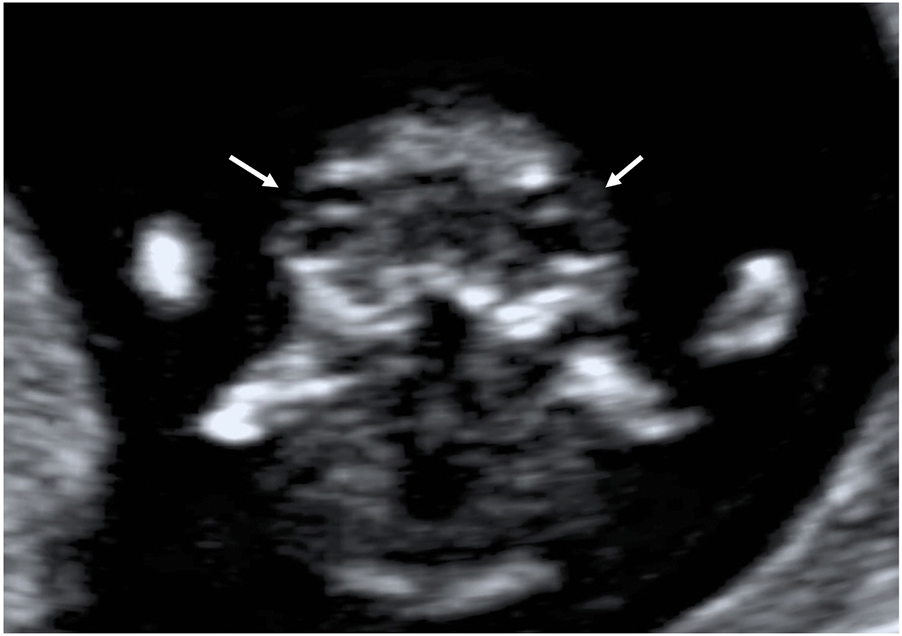

Under normal conditions, the fetal skull appears as an oval-shaped hyperechoic bony structure. The two hemispheres, similar in size, are separated by a straight, uninterrupted midline echo (interhemispheric fissure) on the axial planes. The choroid plexuses should fill the two lateral ventricles on the sides of the midline (butterfly sign on axial view [62]) occupying roughly half or more of the ventricle length/area [63,64] (Figure 1). On the midsagittal view, the anechoic round-shaped diencephalon is visible in the middle of the fetal brain, and the cranial posterior fossa (CPF) structures are just posterior to it, including the brainstem (BS), the 4th ventricle (4V), and the cisterna magna (CM), appearing as three anechoic spaces, roughly similar in size (Figure 2). The biparietal diameter (BPD) could be measured on the axial view in selected cases, mainly for dating purposes.

Axial view of the fetal head and brain.

The hyperechoic oval-shaped skull is visible. The fetal hemispheres are separated by the interhemispheric fissure (arrows). Lateral ventricles (*) containing choroid plexuses (C) are also visible.

Skull and head shape, midline echo, and brain hemispheres, including lateral ventricles and choroid plexuses, should always be evaluated at the routine first-trimester examination. These structures should be preferably assessed on axial planes.

The axial view of the fetal brain should be obtained with the ultrasound beam perpendicular to the interhemispheric fissure, appearing as the midline echo, to evaluate its integrity adequately. In addition, the brain hemispheres should be equal in size, witnessing a proper axial rather than oblique approach, and the plane required for the routine evaluation of the fetal anatomy should be just above the thalami and midbrain to adequately visualize the choroid plexuses and ventricles from frontal to occipital horns.